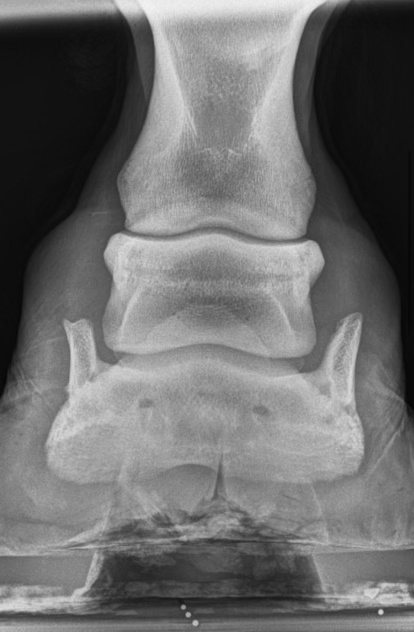

Her: His side bones in both feet are wild

Sidebones are the ossification of collateral cartilage in hoof. It is extremely common – some estimates suggest 80% of all horses have it. 95% of the time, it causes no issues and is not a contributing factor to lameness.

“However, fracture of these cartilages or damage to nearby ligaments may be an issue when lameness is localized to the foot.”

“There are reports of sidebone associated with changes to ligaments elsewhere on the limb, suggesting that sidebone may cause abnormal stress during movement.”

“If the condition is extensive enough, you should carefully consider this horse’s future and be aware that he is at-risk for collateral ligament, distal interphalangeal (coffin) joint, and distal phalanx (pedal bone) injury,”

I looked up an image of a normal hoof x-ray:

Now here is Griffy’s – see if you can spot the difference, it’s subtle: